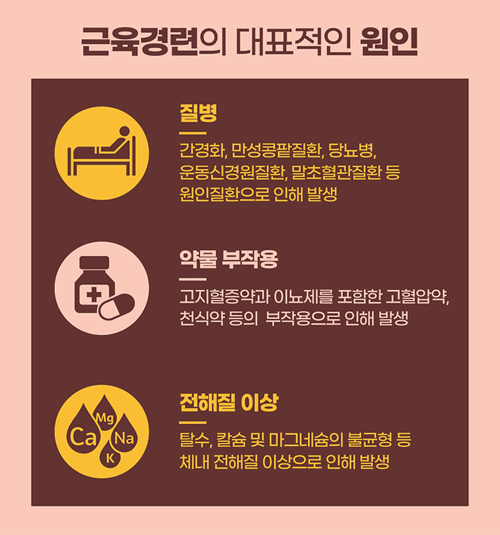

노인인구가 증가하면서 회복이 어려운 퇴행성 질환과 신경질환도 늘어나고 있다. 그중 우리가 외래에서 가끔 만나는 환자들은 파킨슨병을 앓고 있는 환자들이다. 파킨슨병은 걷기가 어려워지고, 팔이나 다리 근육의 떨림이 점점 심해지면서 일상생활에 많은 어려움을 겪는 질병으로 잘 알려져 있다. 따라서 손 떨림, 눈 떨림, 다리 떨림 등 경미한 떨림 증상이 나타나더라도 파킨슨병이 아닙니다. 고민을 안고 병원을 찾아오는 분들을 종종 만날 수 있습니다. 파킨슨병이란 무엇입니까?

파킨슨병은 주로 떨림, 근육 경직, 신체 움직임 둔화 등의 운동 이상을 일으키는 질환이다. 이 질환은 뇌의 신경전달물질인 도파민이 부족해 운동장애 증상이 악화되는 징후를 보인다. 주로 노년층에서 발생하며, 나이가 들수록 파킨슨병 발병 위험이 높아지는 것으로 알려져 있습니다. 파킨슨병은 회복이 쉽지 않지만, 조기에 진단하고 도파민 결핍을 해소할 수 있는 약물로 적절한 치료를 받는다면 큰 문제 없이 생활할 수 있으며 질병의 진행도 완화될 수 있다. 파킨슨병에는 어떤 약물을 주의해야 합니까?